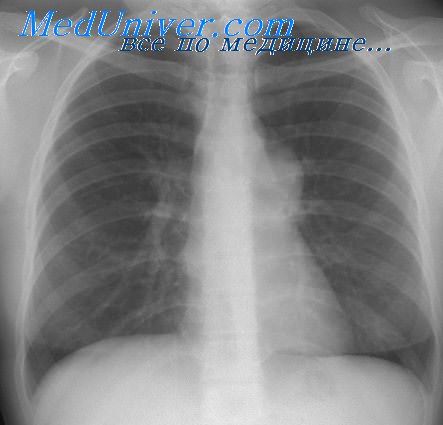

Рентгеновские снимки тератомы средостения: Диагностика и лечение

Раздел: Фотоэссе